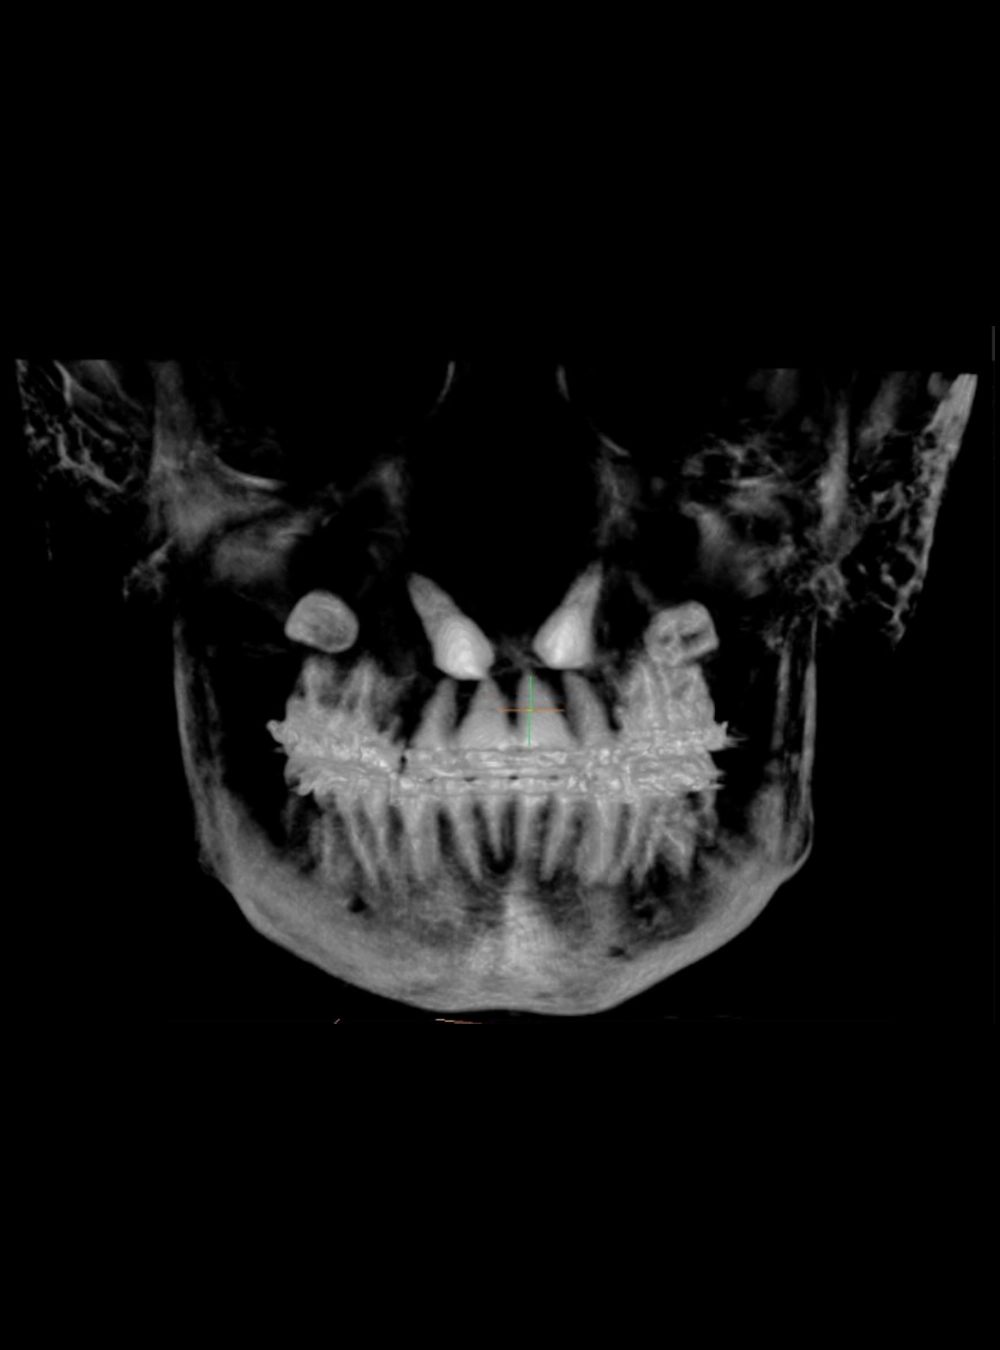

Tecnología de punta en tomografías

Tomografía Volumétrica

Cone Beam (USB o CD)

Dientes Retenidos - Vista RX

Dientes retenidos - Vista Tomografía

Panorámica en Tomografía Cone Beam